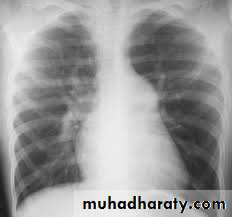

In infantile type ECG and CXR show right ventricular hypertrophy with cardiomegaly and pulmonary edema while in older children they show left ventricular hypertrophy and a mildly enlarged heart

In older children(>8 years) the chest x-ray film may show notching

of the ribs due to the development of collaterals.